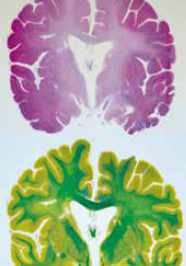

Couleurs spécifiques pour lésions différentes.

Les coupes sont ensuite colorées en fonction des pathologies qu’on souhaite explorer. A la dernière étape du processus, elles sont collées avec de l’albumine sur des plaques de verre.  Les voilà enfin prêtes pour les examens au microscope, la recherche médicale et, en fin de compte, pour enrichir le laboratoire d’une nouvelle pièce. « À ce jour, ces archives ont déjà produit de nombreuses découvertes neuropathologiques. L’une de nos tâches est de les préserver afin qu’elles continuent à stimuler la recherche en matière de troubles neuropsychiatriques », souligne le Pr Constantin Bouras.